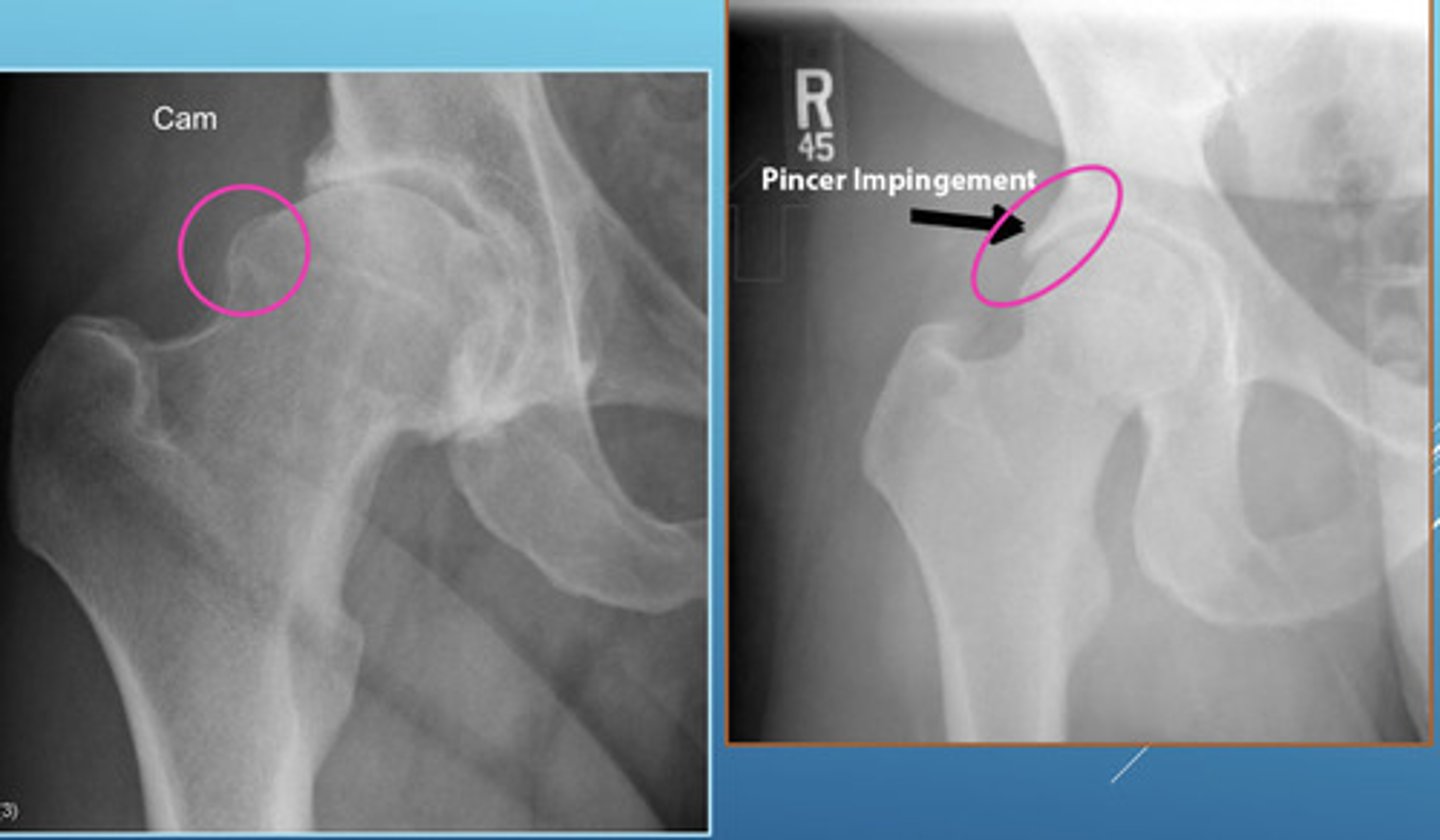

Femoral Acetabular Impingement (FAI)

Condition that characteristically presents with hip pain secondary to mechanical impingement from abnormal hip morphology involving the proximal femur and/or acetabulum

2 Types of FAI Joint Deformities

(1) Pincer Morphology = overcoverage of the femoral head

(2) Cam Morphology = bump formation at the femoral neck and asphericity

Both can co-occur and can lead to FAI and predispose to early OA

Imaging Findings of FAI

— Cam or Pincer morphology

— Pistol grip deformity (Cam)

— Acetabular overcoverage (Pincer)

— Ilioischial line violation (protrusio acetabuli)